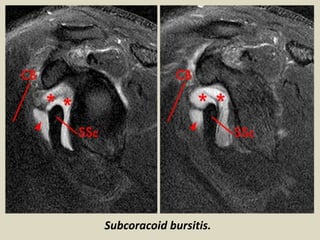

Subcoracoid bursitis.